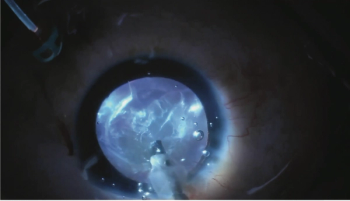

Physicians offer pearls for improving visualisation in eyes using retroillumination techniques.